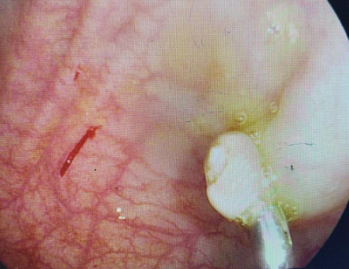

第二天下午,在做好肠道准备后,小恒来到必威官方首页官网betway门诊三楼消化内镜室进行肠镜检查。在进镜距肛门30cm乙状结肠处,发现一枚约1.5×0.6cm枣核大小的息肉,蒂粗约0.5cm,表明红,分叶状。

肠镜下发现约1.5×0.6cm枣核大小的乙状结肠息肉